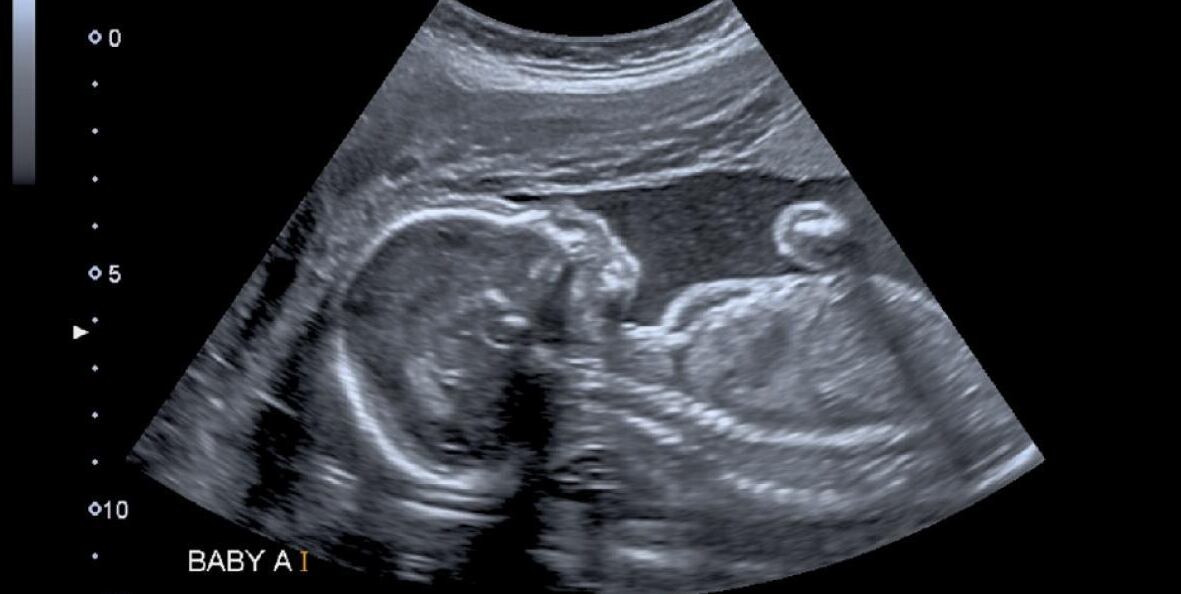

Por tal motivo fue remitida al hospital Ponta Porã, donde le realizaron diversos exámenes y una tomografía en 3D, con la cual le pudieron identificar al feto calcificado, por lo que fue diagnosticada con una condición llamada litopedia.

Lo anterior significaba que tuvo un embarazo ectópico, es decir, que el óvulo fecundado se implantó fuera del útero, pero su desarrollo continuó hasta la muerte fetal, lo que lo lleva a la calcificación, según se lo explicó el Hospital Regional de Ponta Porã a CNN.